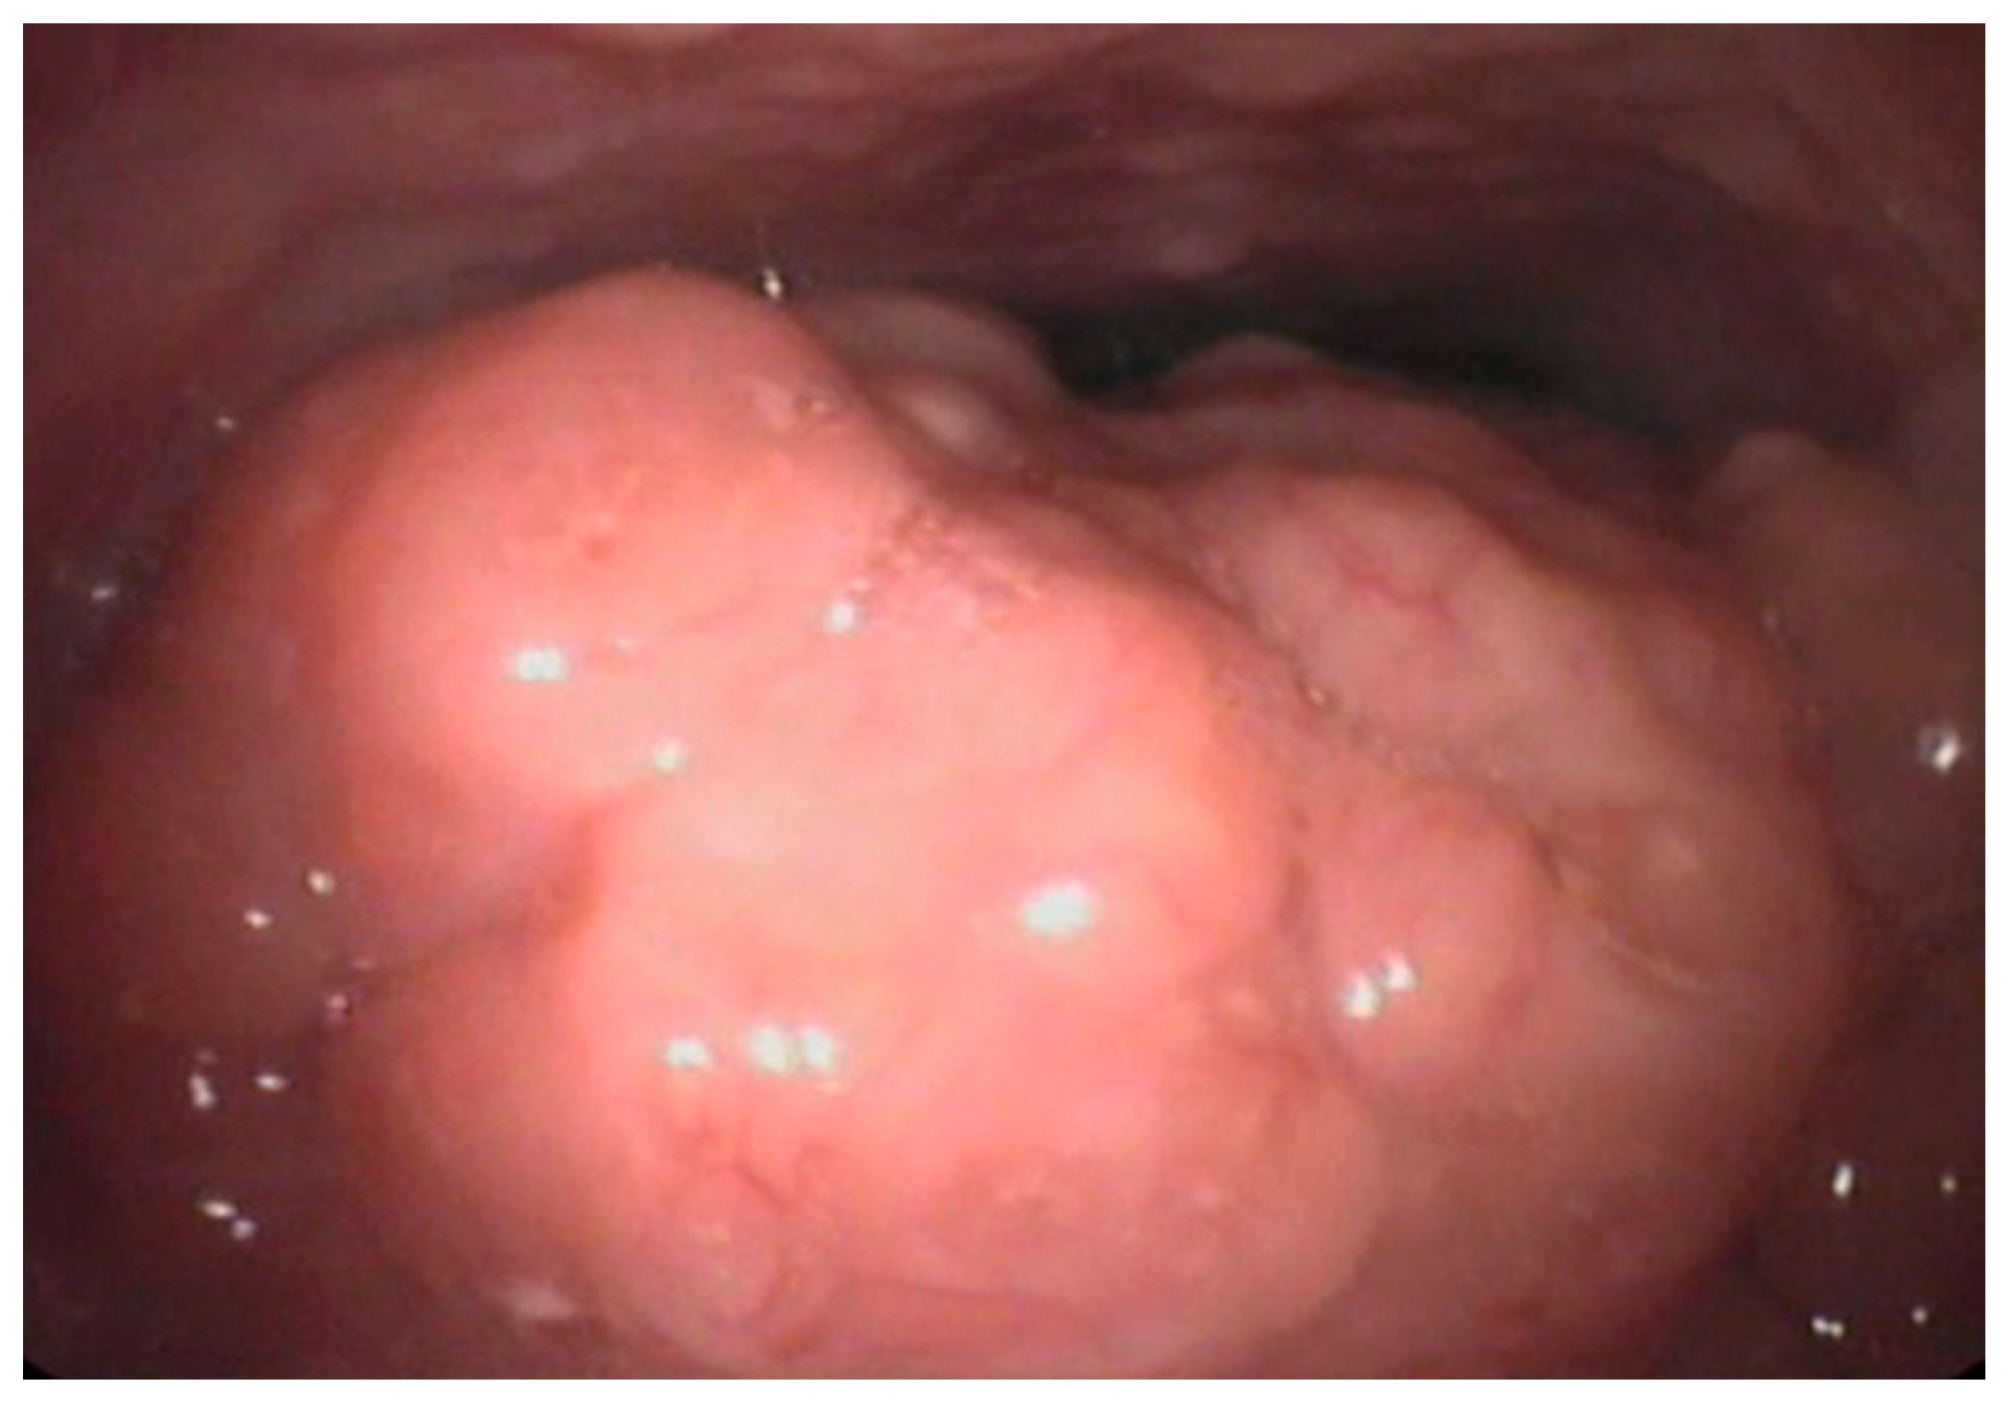

| Grade | Description |

|---|---|

| 0 | No tonsils seen |

| I | In tonsillar fossa |

| II | Visible beyond anterior pillars |

| III | Extended ¾ of way to midline |

| IV | Completely obstructing airway (kissing tonsils) |